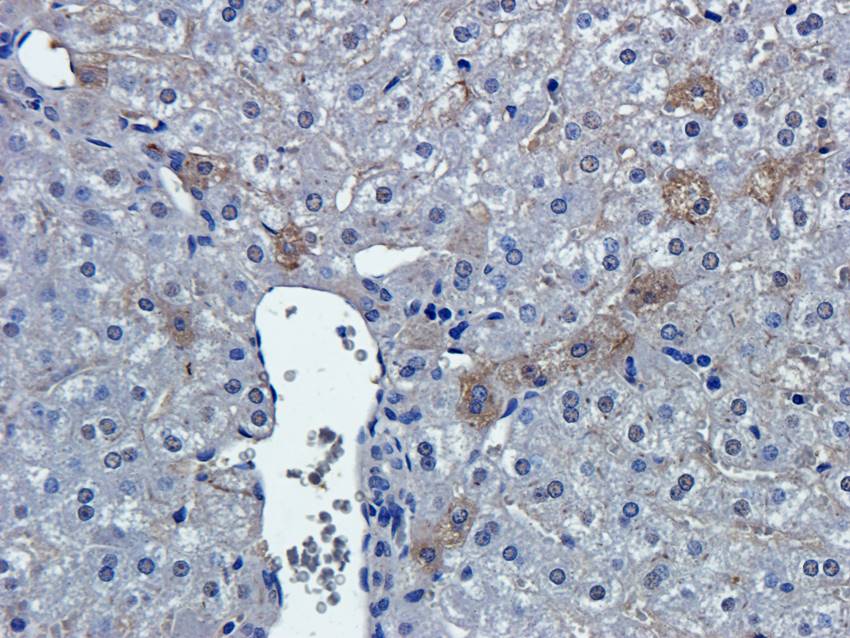

IHC staining of FFPE human brain with Ubiquitin antibody (clone PBQN-1). Required HIER: boil tissue sections in pH9 10mM Tris with 1mM EDTA for 10-20 min followed by cooling at RT for 20 min.